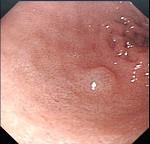

问题 男,70岁,剑突下疼痛伴进行性咽下困难1个月,消瘦、乏力明显,粪隐血持续阳性,内镜及影像检查如下图,诊断为 ( )

选项 A.胃黄斑瘤 B.贲门息肉 C.胃溃疡 D.贲门癌 E.胃癌

答案 E